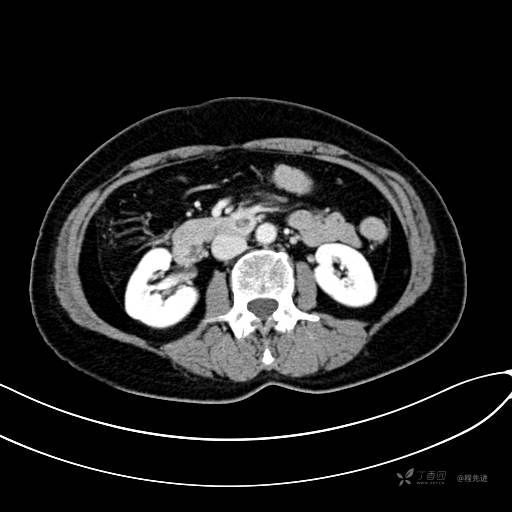

CT增强动脉期